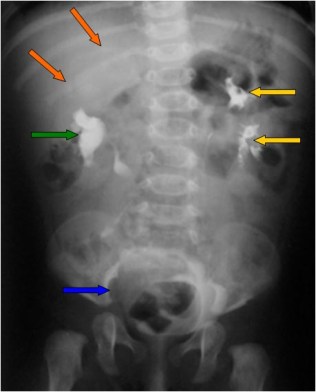

SIGNOS DE LA COLMENA Y DEL HERALDO

Signos de fístula colovesical en la cistografía. El extremo vesical de la fístula se asocia con la imagen de una deformidad biconvexa triangular (flechas verdes) que acaba en un punto bien definido, como si se insinuase el contraste en la boca de la fístula. De hecho puede verse contraste fuera de la vesícula, por encima de ese ángulo que forma el borde superior vesical.

En nombre del Signo de la colmena se debe a que la vejiga queda deformada adoptando una forma que recuerda a la celda de una colmena.